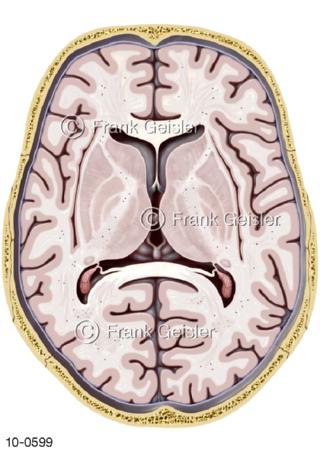

Bildergalerie Nervensystem

Bilder zum Nervensystem,dem Gehirn, Teil des zentralen Nervensystem, Zentralnervensystem ZNSmit Rückenmark, Abbildungen zum Nervengeflecht (Nervenplexus), die Verflechtungen von Nervenfasern, aus der Wirbelsäule hervortretende Nervenäst sowie Nervenzellen der Nerven